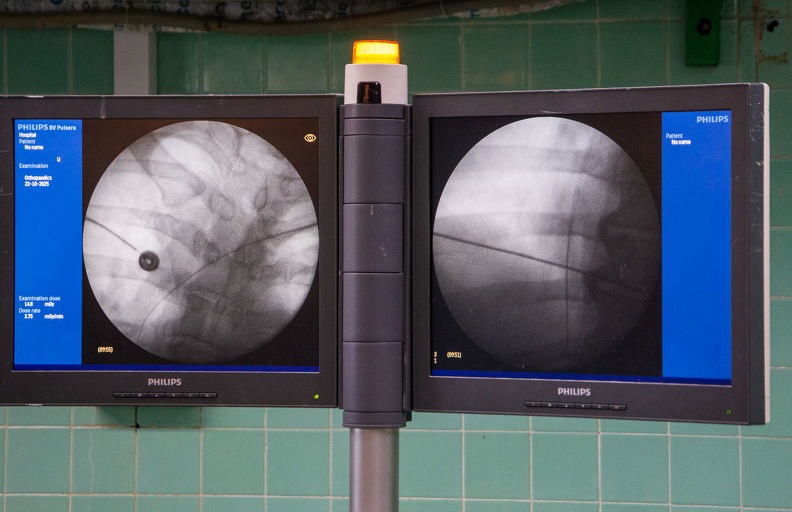

Pinar del Río, 22 oct (ACN) Por primera vez en Pinar del Río hoy se realizó una cirugía de colocación de desfibrilador automático implantable (DAI), proceder para el cual los pacientes debían ser intervenidos en instituciones asistenciales de La Habana.

Efectuada en el hospital provincial Abel Santamaría Cuadrado, la operación estuvo a cargo de la doctora Ana Mengana Betancourt, especialista en Cardiología del hospital Hermanos Ameijeiras, acompañada por un equipo de profesionales vueltabajeros.

La manera de implantación del DAI es bastante parecida a la del marcapasos, pero los electrodos son más gruesos; se coloca dentro del corazón, detecta la arritmia y en dependencia de la duración y la frecuencia la choca o le da una terapia que se llama ATP, explicó a la prensa Mengana Betancourt.

En Pinar del Río normalmente se ponen marcapasos, pero es la primera vez que se instala este equipo, apuntó la doctora Maylín Vilaú Jiménez, especialista en segundo grado de Cardiología del "Abel Santamaría Cuadrado" y una de las que participó en la intervención.